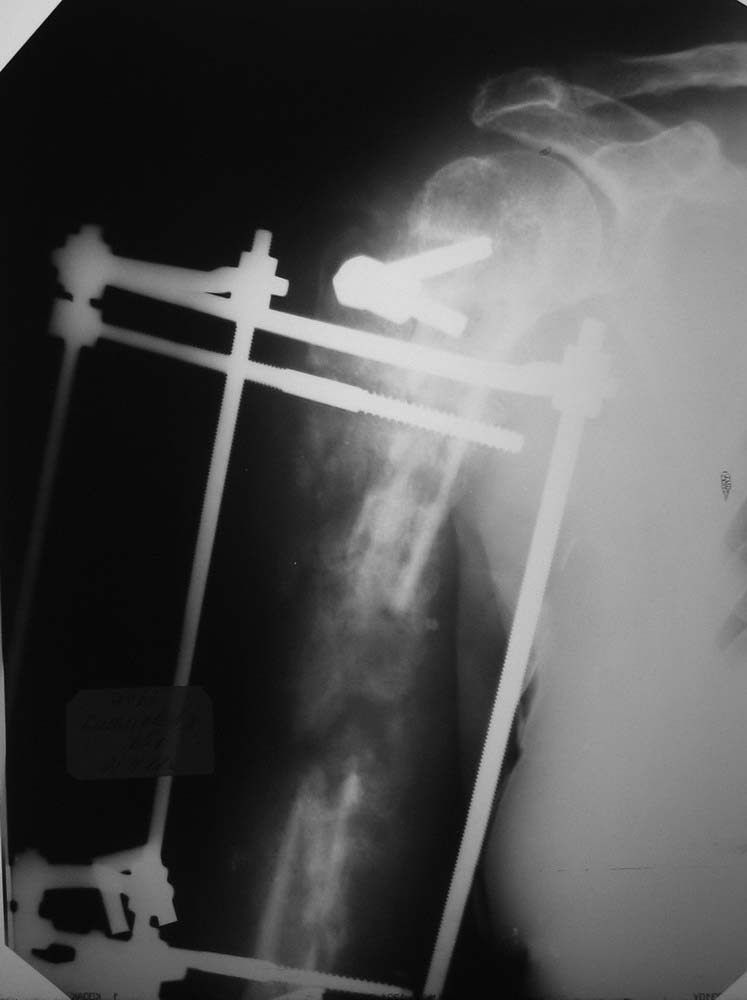

В приложении один из возможных вариантов решения проблемы на плече.

Вариантов тут довольно много, интрамедуллярный остеосинтез, наверно, в каком-то из воплощений обеспечил бы максимально быструю независимость пациента и возможность движений в суставах. Например, можно на пару недель установить санирующий спейсер, а потом перейти на Fixion. Или сделать сразу блокируемый штифт с антибиотиковым покрытием. Или неблокируемый, но тоже с цементом. Зависит в т.ч. от состояния отломков на всем протяжении, чего пока не видно.

Виктор! Начну с вопроса - что остановило первично заштифтовать, а не идти открыто? При такой установке пластины, Вы сразу дали шанс сломаться всему повторно. Если оставлять в аппарате, то срастаться будет лет так надцать (дефект около 10 см). Сохраните длину конечности и синтезируйте штифтом, ранняя нагрузка и штифт будет выполнять у Вас роль внутреннего эндопротеза и пусть срастается, главное будет рабочая рука, а не красивый рентген снимок.